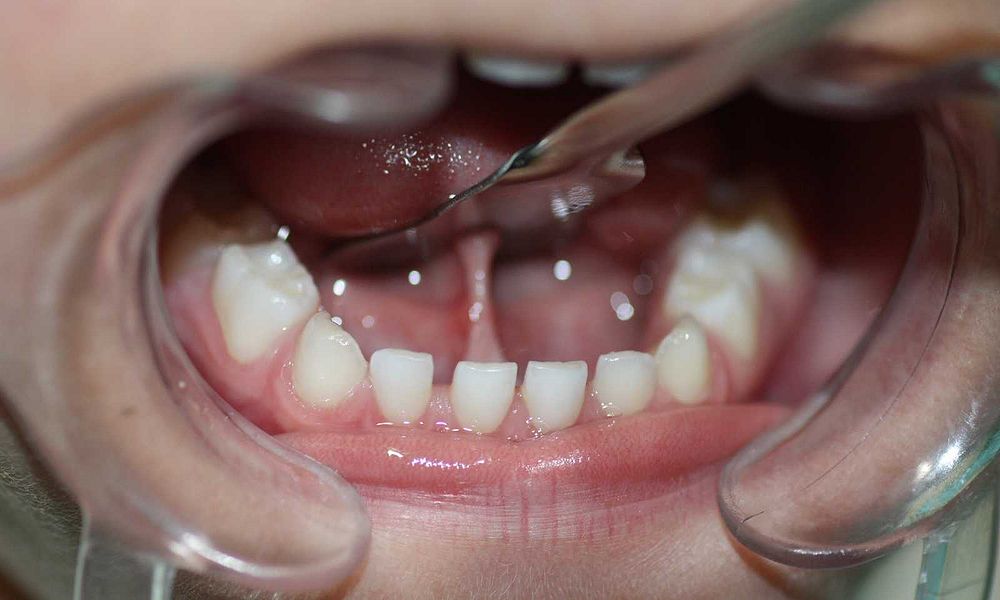

- Problemas de oclusión

Como es sabido cada niño en la primera etapa tiene un paladar estrecho y gracias a los movimiento linguales se abre de manera paulatina. En caso que el frenillo corto imposibilite el movimiento de lengua, se genera un desarrollo anómalo de la estructura maxilofacial y ocasionará problemas de oclusión.

- Paladar muy estrecho, dando lugar a maloclusiones , apiñamiento dental, rotaciones de las piezas dentarias.

- Presencia de un diastema en los dos dientes incisivos inferiores.